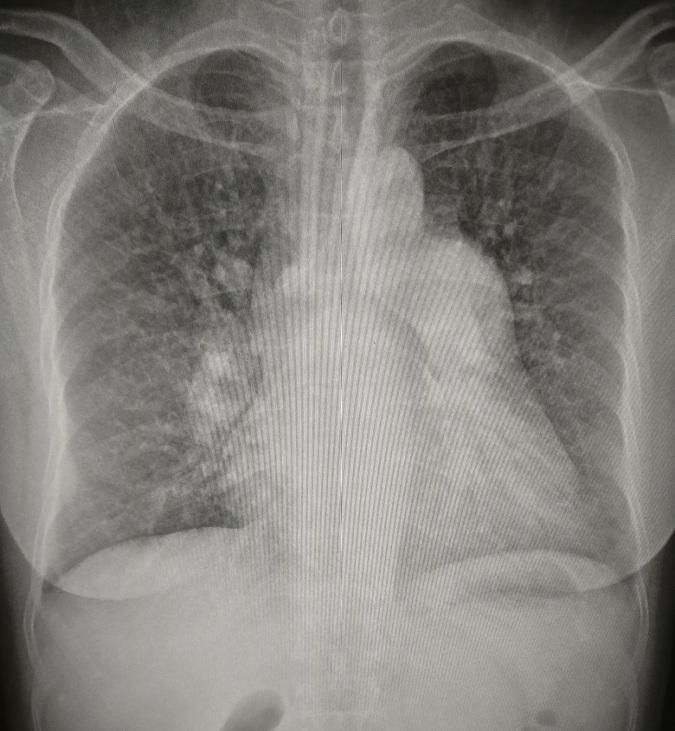

1.左心室增大

常见于高血压病、主动脉瓣病变、二尖瓣关闭不全、先天性心脏病如动脉导管未闭等。见图1。

图1 正位片见左心缘延长,心尖左下移位